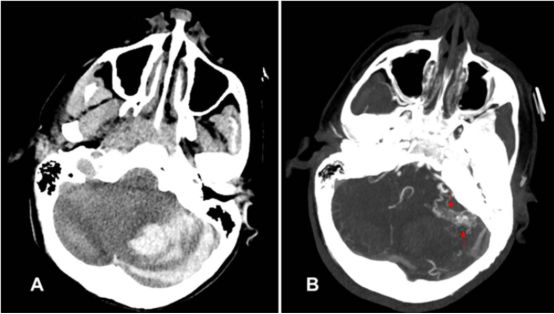

4.儿童未确诊大脑动静脉畸形引起的急性致命性脑出血:单中心回顾性研究

Acute fatal hemorrhage from previously undiagnosed cerebral arteriovenous malformations in children: a single-center experience.

DOI: 10.3171/2018.3.PEDS1825.

动静脉畸形(AVM)引起的脑出血最严重的并发症就是死亡,该单中心研究分析之前未确诊的AVM出血致突发死亡的发生率,明确相关的临床和影像学因素。作者回顾分析了2006-2017年间之前未确诊的AVM首次颅内出血的57位患者,平均年龄10.8岁。其中7位(12%)患儿(平均年龄11.5岁)的脑出血导致死亡,死亡患儿罹患后颅窝AVM的概率是存活患儿的4倍,未发现明显的诱发因素(如剧烈运动、外伤等),死亡的7例患儿中3例在入院前出现过心脏骤停。42/50例(84%)存活的患儿最后行AVM切除术,这些数据说明积极主动的处理儿童动静脉畸形是非常必要的。

![]()

左侧小脑半球AVM突发出血致患儿死亡